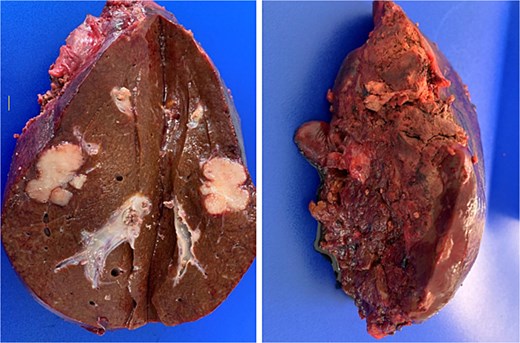

Pathological analysis of the surgical specimen later revealed that R0 resection had been achieved [full TNM classification for the cancer of the upper rectum was pT3 pN1b (3/21) pM1a (HEP)] (Fig. 3).

Post-resection specimen of the right hepatic lobe (segments V–VIII) showing multiple metastases from colorectal carcinoma.